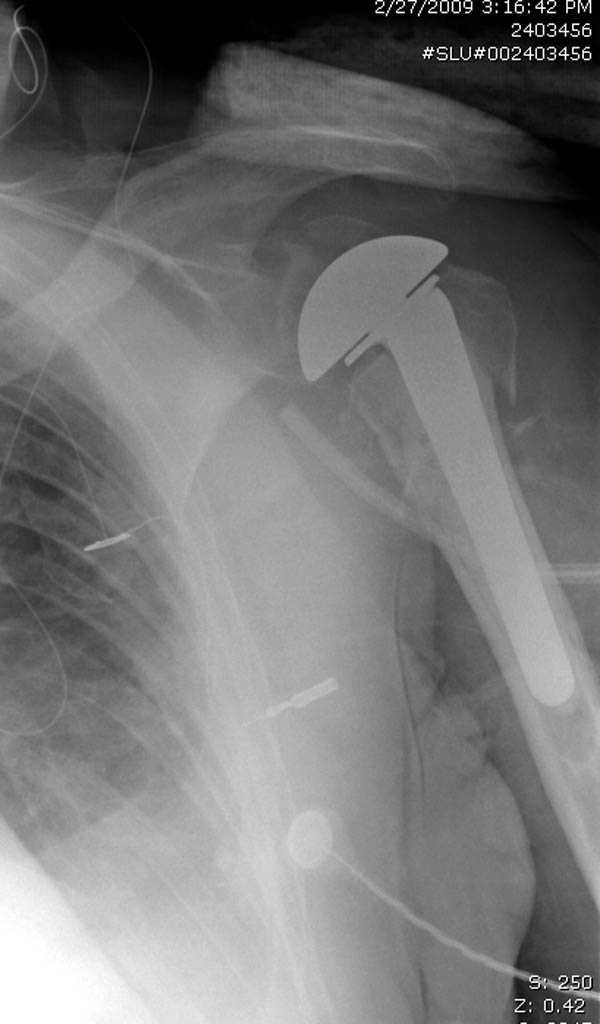

Пациентка Б.1953 г.р., врач-терапевт. Травма 27.11.08г. Падение с высоты роста. Выявлен закрытый не осложненный оскольчатый перелом хирургической шейки левого плеча со смещением. 02.12.08г. оперирована. Выполнена открытая репозиция и остеосинтез пластиной LCP Деост с дополнительной фиксацией отдельно лежащего фрагмента винтом. Послеоперационный период протекал без особенностей, заживление раны первичным натяжением. Швы сняты через 10 дней. Иммобилизация левой верхней конечности клиновидной подушкой 4 недели. По окончании срока – рентген-контроль и умеренная разработка плечевого сустава. В течении месяца функция левого плечевого сустава восстановилась удовлетворительно: поднятие руки до 110 гр., отведение - 90 гр. и до 110 гр. отведение с лопаткой. Отведение руки назад – 20 гр. Наружная и внутренняя ротация – 20 гр. Пациентка по настоянию самостоятельно вышла на работу. 27.03.09 при контрольном осмотре жалоб не предъявляет, болевой синдром в левом плечевом суставе отсутствует. Отведение плеча активно до 90 гр, пассивно с лопаткой до 110 гр., поднятие – 110 гр, отведение назад 20 гр, наружная и внутренняя ротация по 20 гр. На контрольных рентгенограммах отмечается смещение металлоконструкции, ротация головки плеча с приведением дистального отломка на 13 гр. и смещением к зади на 30 гр. Рентгенограммы прилагаются. Ваш взгляд на дальнейшую тактику лечения пациентки?

Здесь пример открытой репозиции 57 летнего с переломом плеча (1,2) смещение обнаружено на интероперационном снимке. При нормальной прямой проекция (3) угловое смещение обнаружили в аксиальной проекции (4)

После устранения смещения пластина установлена выше (5,6,7) и финальные снимки (8,9,10)

дополнительные снимки по протезированию